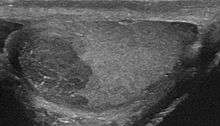

Intratesticular masses that appear suspicious on an ultrasound should be treated with an inguinal orchiectomy. The pathology of the removed testicle and spermatic cord indicate the presence of seminoma and assist in the staging. Tumors with both seminoma and nonseminoma elements or that occur with the presence of AFP should be treated as nonseminomas. Abdominal CT or MRI scans as well as chest imaging are done to detect for metastasis. The analysis of tumor markers also helps in staging.[9]